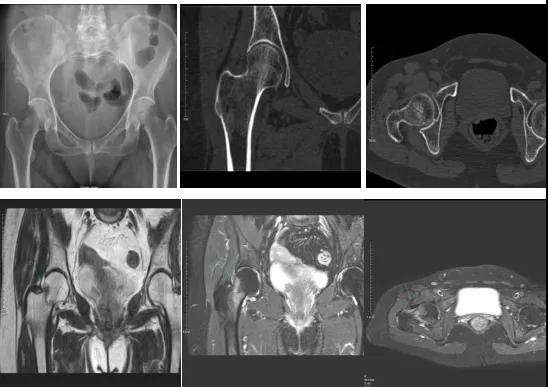

DR示:右側股骨頸未見明顯骨折征象。CT右側股骨頸骨質密度不均。患者體征明顯,為明確診斷,行MRI檢查。MRI示:右側股骨頸T1WI呈低信號,脂肪抑制序列呈高信號;提示右側股骨頸隱匿性骨折。